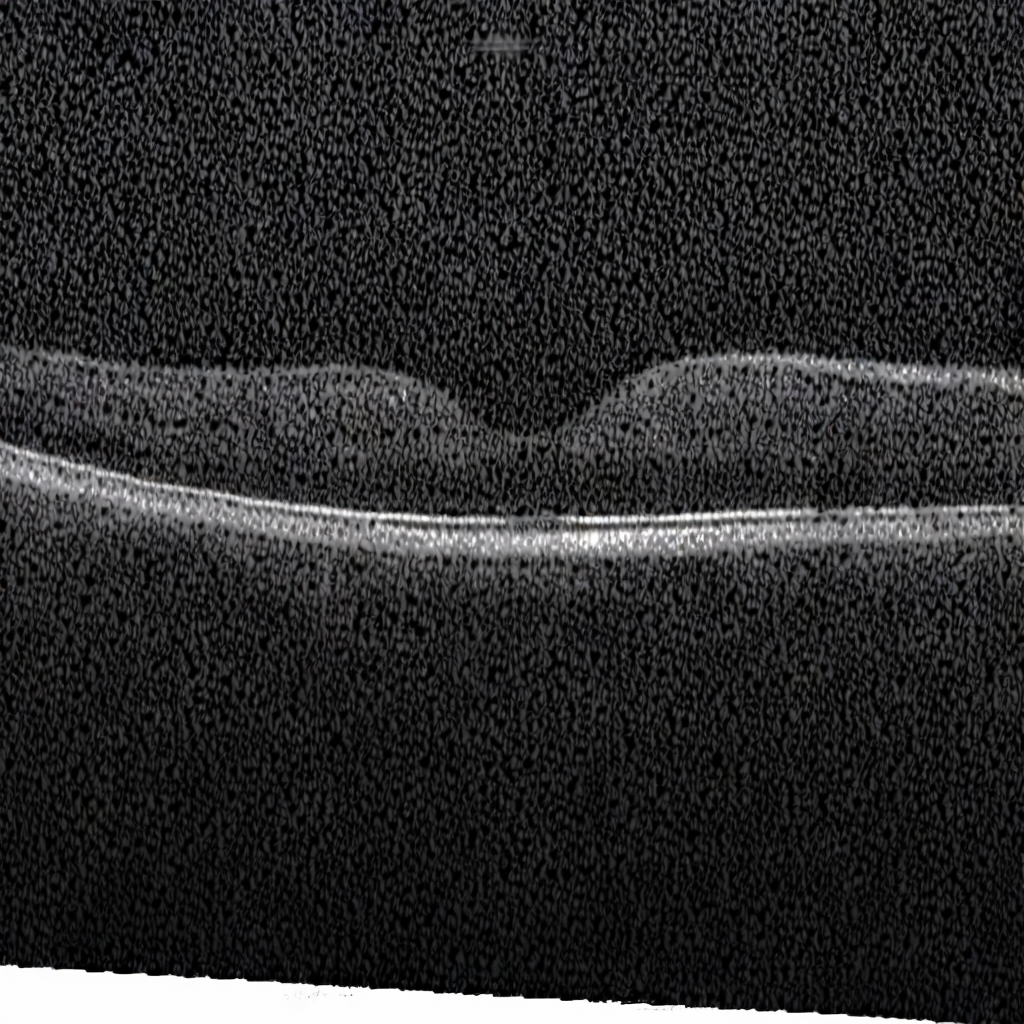

Diffusion models have recently gained significant traction due to their ability to generate high-fidelity and diverse images and videos conditioned on text prompts. In medicine, this application promises to address the critical challenge of data scarcity, a consequence of barriers in data sharing, stringent patient privacy regulations, and disparities in patient population and demographics. By generating realistic and varying medical 2D and 3D images, these models offer a rich, privacy-respecting resource for algorithmic training and research. To this end, we introduce MediSyn, a pair of instruction-tuned text-guided latent diffusion models with the ability to generate high-fidelity and diverse medical 2D and 3D images across specialties and modalities. Through established metrics, we show significant improvement in broad medical image and video synthesis guided by text prompts.

In this work, we focus on the ability of LDMs to generate novel datasets to overcome class imbalances traditionally associated with medical data, and potentially reduce the need for manual annotation of medical 2D and 3D data. We present MediSyn, a pair of text-guided latent diffusion models for broad medical 2D and 3D modality synthesis. To overcome the scarcity of labelled medical data, we leverage a vast corpus of more than 5 million image-caption pairs and 100,000 video-caption pairs collected from the public domain across numerous medical specialties, and integrate comprehensive natural language annotations to develop a pair of versatile diffusion models for the medical domain.

Since their introduction, generative models have had a rich history in the medical field, ranging from anomaly detection and image denoising [21, 22], to image reconstruction and segmentation [23, 24]. For instance, DDPMs have been trained to convert MRIs to CTs for soft tissue injury [25], synthesize labeled brain MRIs for training segmentation models [26], denoise OCTs to erase visual artifacts [27], and reconstruct images for accelerated MRI scans [28].

We assembled a set of 5,785,333 medical image-caption pairs, covering 8 specialties and 9 imaging modalities, to train Medisyn’s 2D model. We reserved an additional 1000 image-caption pairs (125 pairs from each specialty) for model evaluation.

| Magnetic Resonance Imaging (MRI) | 699,105 |

Our findings demonstrate Medisyn’s remarkable ability to generate high-fidelity and diverse medical images, image sequences and volumetric scans across various medical subspecialties and imaging modalities. Other medical text-driven diffusion models, such as TauPETGen [42] for tau PET images and GenerateCT [43] for chest CT volumes, have proven successful in generating high-quality images that accurately depict anatomical features and clinical conditions. However, these models are constrained to a single imaging modality and anatomical region, thereby restricting their applicability. Moreover, they were trained on relatively small datasets sourced from a limited number of institutions, which could lead to more biased outputs. In contrast, Medisyn, having been trained on one of the largest publicly accessible medical image and video datasets to date, is equipped to synthesize data that cover numerous medical disciplines, population groups, and disease states. Leveraging our two models, we can synthesize new medical datasets as well as augment existing ones, potentially improving a wide array of medical machine learning tools, both general and specialized. Additionally, our models can minimize the need to repeatedly fine-tune on specific datasets for generating different imaging modalities, thus reducing computational costs for academic labs.

In summary, we introduced a pair of text-conditional LDMs trained on an extensive medical image and video dataset covering various medical subspecialties and imaging modalities. By generating high-fidelity and diverse medical 2D and 3D images, Medisyn illustrates the potential for a singular framework to broadly address the challenge of data scarcity in healthcare.